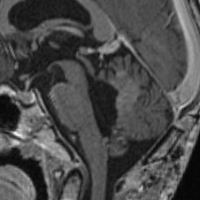

乳児にできた視神経膠腫です(左側の写真)。腫瘍が眼窩内にとどまっていて左の目はすでに失明していましたから,腫瘍を手術で全部とりました(右側の写真)。このような手術は腫瘍が反対側の視神経にいかないようにするために視神経交差のところで切り離すので,開頭手術が必要です。眼球も残っていますし再発はありません。